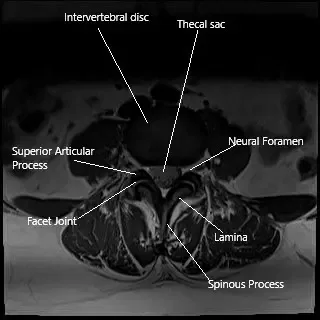

MRI axial section showing the facet joint.

Facet joints connect the vertebrae at the back of the spine and allow for smooth movement. They are surrounded by a capsule that produces synovial fluid—a lubricant that helps the joints move easily.

The facet joints are located behind each vertebra and guide motion in the spine. Each joint has smooth cartilage and is enclosed by a capsule filled with synovial fluid for lubrication.